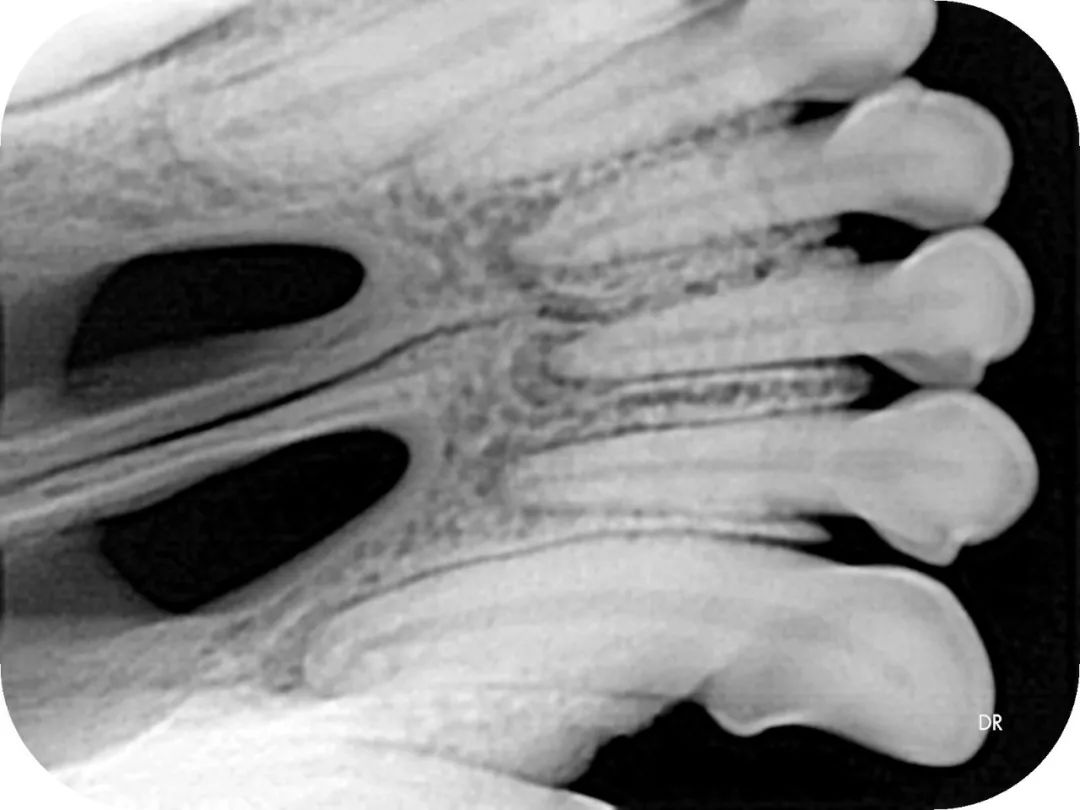

▲院内新进牙科DR设备之一

▲部分牙科DR效果展示图(可左右滑动)

什么是DR?

DR检查是影像科常用的一种检查方法,它又称为数字化X射线摄影系统,相对于传统的拍片子检查,它的辐射量更小,检查的时间更短,片子的质量也更高